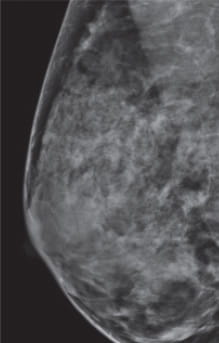

Radiologists classify breast density using a four-level density scale, as determined by a mammogram:

- Category C: Heterogeneously dense

- Category D: Extremely dense

Having dense breast tissue may increase your chance of getting breast cancer. Dense breasts also make it more difficult for doctors to spot cancer on mammograms. Dense tissue appears white on a mammogram; lumps, both benign and cancerous, also appear white. So mammograms can be less accurate in women with dense breast tissue.

Fibroglandular density is determined by the radiologist who reads a mammogram. The radiologist assigns each mammogram to one of the four categories of breast density. If your mammogram shows that you have heterogeneously dense or extremely dense breast tissue, you will receive a letter notifying you that you have dense breasts. You can speak to your primary care physician about your risk and your breast cancer screening options.